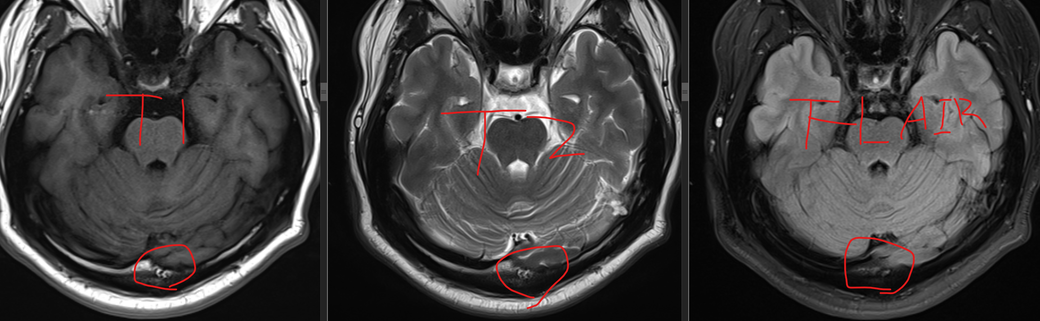

순서대로 T1 T2 FLAIR입니다

T1에서 밝고 T2에서 덜 밝으면 지방 아닌가요?

FLAIR에서는 지방이 안보이나요?

병원에서는 판독지에 해당 내용이 없고

신경과 선생님은 증상과 별 상관 없을거라고 넘어가셔서

뭔지 궁금해서 올립니다

후두부에 위치하는 음영으로 임상적으로 큰 의미 없는 영상소견으로 보입니다.